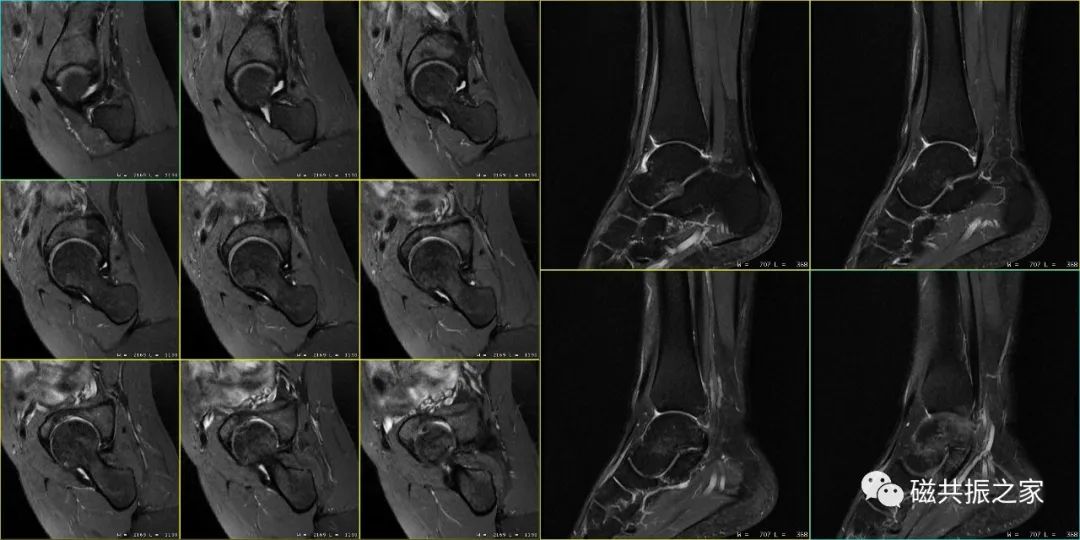

在进行四肢关节的扫描摆位时,首先要让被检者处于最为舒适的状态才能顺利地完成整个检查,特别是对于一些比较特殊的被检者。如上图△,对于该呈90°的肘关节的扫描,我们需要考虑选择何种线圈,被检者处于何种体位才能获得比较理想的图像质量。

除此之外,摆位时还需选择合理的线圈,抓住你需要观察的重点等,在其规范化摆位的基础上做到个性化的摆位。如上图△,对于足踝部的扫描,做好其压脂的均匀性是其难点之一,那么我们在进行该部位扫描时怎样摆位才能获得比较优异的图像。